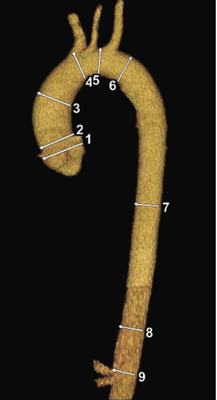

Аорта характеризуется исключительной пропускной способностью, обеспечивая циркуляцию крови в объеме почти 200 миллионов литров в течение жизни человека. В дополнение к проводящей функции, в аорте также осуществляется регуляция и контроль системного сосудистого сопротивления и частоты сердечных сокращений за счет барорецепторов, расположенных в области дуги и восходящего отдела. Можно утверждать, что аорта выполняет роль «второго сердца» во время диастолы (функция Виндкессела), то есть сглаживает осцилляции давления, обусловленные интермиттирующим выбросом из левого желудочка, что наиболее важно не только для адекватной коронарной перфузии, но также необходимо для других органов и тканей. В норме диаметр аорты обычно не превышает 40 мм и характеризуется постепенным сужением в дистальном направлении. Данные параметры зависят от ряда факторов, включая возраст, пол, площадь поверхности тела и уровень артериального давления. Верхняя граница нормального значения диаметра корня аорты (99-процентиль) составляет 40 мм у мужчин и 34 мм у женщин. С возрастом в течение каждого десятилетия происходит увеличение размеров корня аорты примерно на 0,9 мм у мужчин и 0,7 мм у женщин соответственно.

- 1 — Синусы Вальсальвы

- 2 — Синотубулярное соединение

- 3 — Восходящая аорты

- 4 — Начало дуги аорты

- 5 — Середина дуги аорты (место между левой общей сонной артерией и левой подключичной артерией)

- 6 — Начало нисходящей аорты

- 7 — Середина нисходящей аорты (среднее значение между пунктом №6 и №8).

- 8 — Нисходящая аорта на уровне диафрагмы

- 9 — Брюшная аорта на уровне чревного ствола